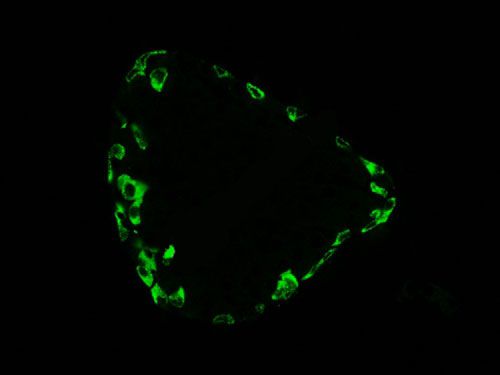

熒光顯微鏡是免疫熒光的基本工具。它是由光源、濾板系統和光學系統等主要部件組成。是利用一定波長的光激發標本發射熒光,通過物鏡和目鏡系統放大以觀察標本的熒光圖像。

正置顯微鏡型號:NIKON Eclipse ci;軟件:NIS_F_Ver43000_64bit_E;成像系統:NIKON digital sight DS-FI2。可選擇100×、200×和400×不同放大倍數。共配置紅、綠、藍三個通道:DAPI(EX激發340-380,BA發射435-485);FITC(EX激發465-495,BA發射515-555);G-2A(EX激發510-560,BA發射590)

實驗結果展示:

(3)實驗結果:圖片×6,每張圖片包括merge圖,單通道圖(常規選擇同視野下200×3、400×3)